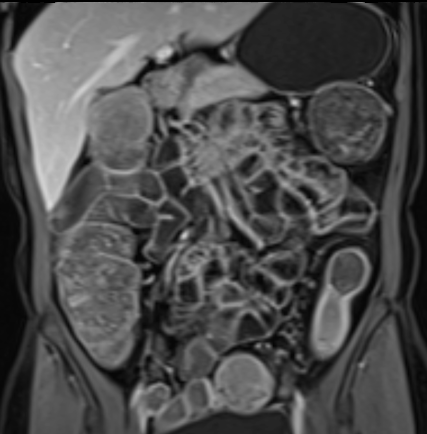

Bệnh nhân nữ 48 tuổi, đang điều trị bằng thuốc kháng TNF, được chỉ định nội soi đại tràng.

Phát hiện hẹp lòng ruột ở đại tràng sigma, không thể vượt qua được khi nội soi.

MR-enterography được thực hiện để đánh giá mức độ lan rộng của chỗ hẹp.

Cuộn qua các hình ảnh.

Ruột non bình thường, nhưng ghi nhận các đoạn hẹp ở đại tràng xuống và đại tràng ngang.

Cả hai đoạn hẹp đều có thành ruột dày đến 8 mm và ngấm thuốc rõ rệt theo kiểu niêm mạc ở đại tràng xuống và kiểu phân lớp ở đại tràng ngang.

Giãn ruột trước chỗ hẹp được ghi nhận ở cả hai đoạn.

Do các chỗ hẹp này không hiện diện khi nội soi đại tràng trước khi điều trị kháng TNF, nhiều khả năng chúng đã hình thành trong quá trình điều trị.

Do đó, quyết định phẫu thuật cắt đại tràng gần toàn bộ với miệng nối hồi-sigma đã được đưa ra.